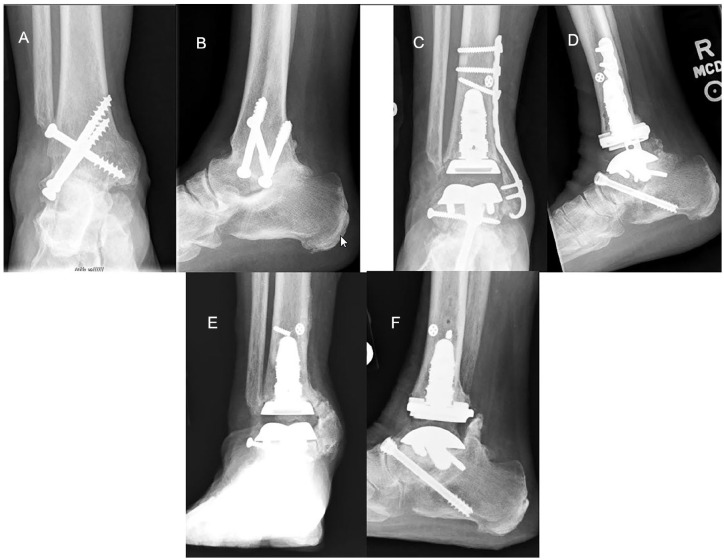

Methods: Between May 2010 and August 2019, 27 patients underwent conversion using a prosthesis with an intramedullary tibial component, 21 of which were available for the study. Six patients had a deficient distal fibula, and 5 were available for follow-up. Our primary outcome measure was having a total ankle arthroplasty in place. Secondary outcomes were evaluated postoperatively with a visual analog scale, the American Orthopaedic Foot & Ankle Society (AOFAS) ankle and hindfoot score, a satisfaction survey, and radiographic assessment of the arthroplasty and any concomitant hindfoot fusions.

Results: Mean follow-up for all patients was 7.6 (2.6-11.8) years, with follow-up of the deficient fibula group of 8.2 (4.9-11.8) years. Complications included malleolar fracture with or without subsequent surgery (n = 5), varus deformity (n = 1), and wound dehiscence or infection (n = 2). At final follow-up, all patients, including the 5 with a deficient distal fibula, had an intact ankle arthroplasty, although 3 with intact fibulas had undergone prosthetic revision. Postoperative dorsiflexion was 4.5 ± 5.1 degrees and plantarflexion 20.9 ± 13.37 degrees. There were no pseudarthroses in the 11 patients with concomitant hindfoot arthrodesis. Mean (±SD) VAS score was 4.4 ± 3.0 and AOFAS score was 71.2 ± 21.7. Sixty-seven percent reported that they were satisfied or very satisfied, with 16% dissatisfied or very dissatisfied. One of the deficient fibula patients was very dissatisfied. Seventy-six percent had no limitations with activities of daily living and two-thirds of those had no limitations at all.

Conclusion: Consistent with previous studies, we find that total ankle arthroplasty can be a satisfactory salvage procedure for patients with a failed ankle arthrodesis. Unlike previous reports, we observed high prosthetic retention in patients with a deficient fibula, although pain relief and range of motion outcomes were mixed, and some patients required revision surgery. These findings should be interpreted in light of the intrinsic limitations of a small sample size, lack of preoperative comparison data, and incomplete follow-up in the deficient fibula group.